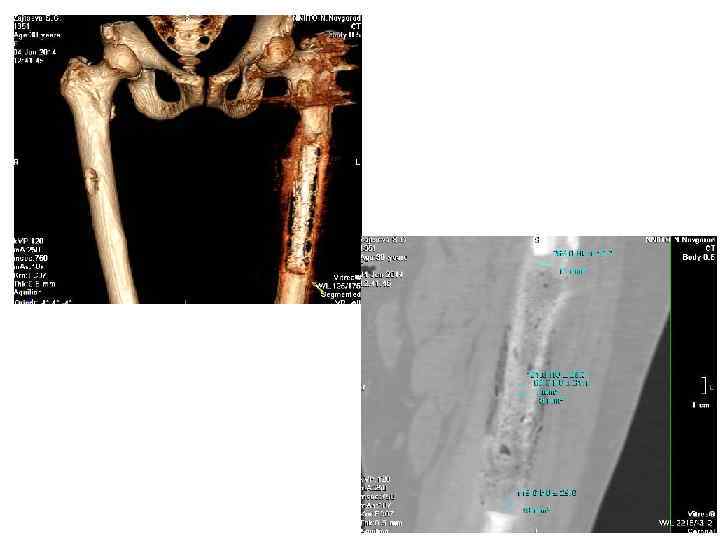

Ортопедическая хирургия реконструкция вертлужной впадины • Напечатанные 3 D модели используются для анализа переломов и определения точного местонахождения и траектории винтов выравнивания и пластин фиксации.

В качестве одного из дальнейших направлений использования 3 D печати в медицине является применение биосовместимых материалов, обладающих свойствами костной ткани.